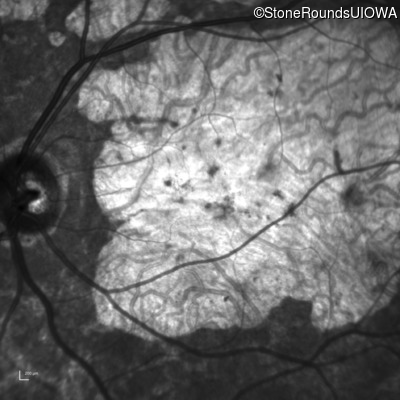

Infrared Fundus Photograph - Right - 20/200 +1 sc

Exemplar

Infrared Fundus Photograph - Right - 10/125 sc